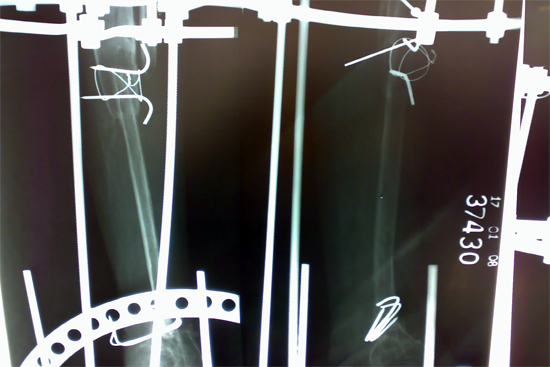

Tibialisation Of Fibula